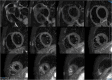

"Cases of SCMR" is a case series on the SCMR website (https://www.scmr.org) for the purpose of education. The cases reflect the clinical presentation, and the use of cardiovascular magnetic resonance (CMR) in the diagnosis and management of cardiovascular disease. The 2022 digital collection of cases are presented in this manuscript.